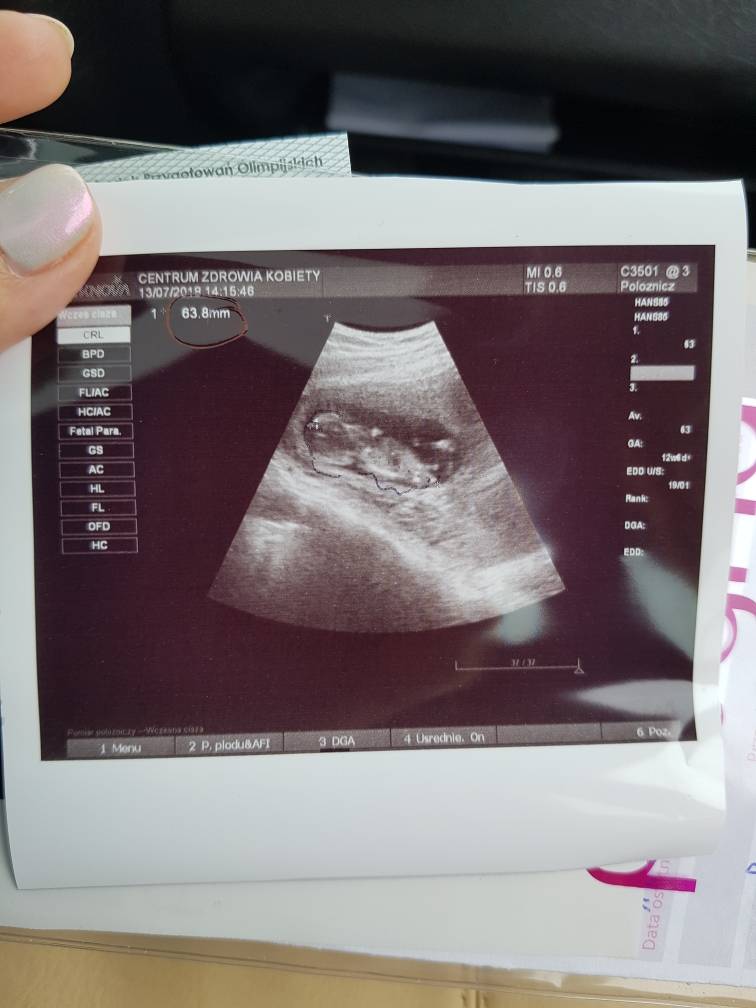

Hej ciężarówki [emoji16] jestem po wizycie [emoji4] wszystko jest ok [emoji4] słyszeliśmy już serduszko [emoji173][emoji173] maleństwo ma prawie 7 cm [emoji4][emoji4] i termin z USG dzisiejszego też jest o 2 dni szybszy niż z OMz OM na 21.01 A z dzisiejszego USG 19.01 [emoji4] kolejna wizyta 10.08.

Zobacz załącznik 877217